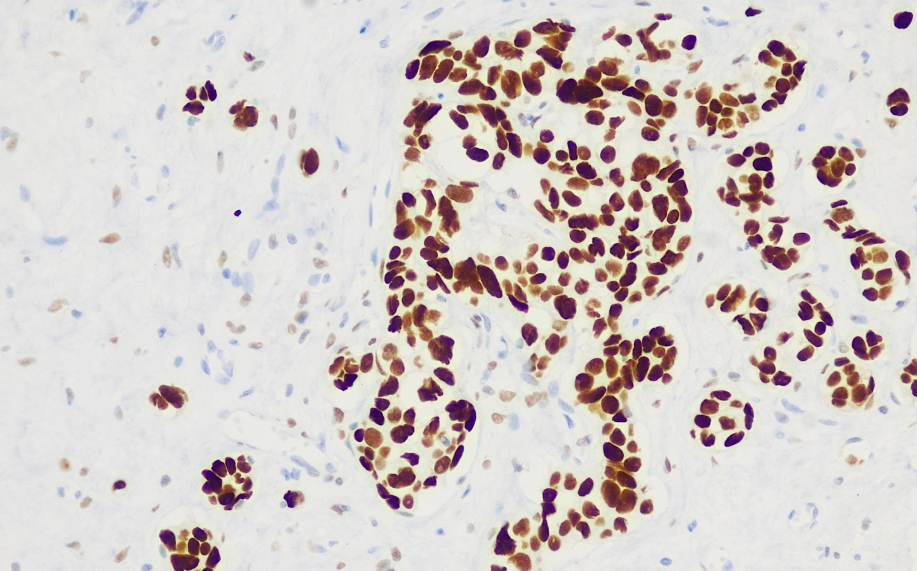

Cell localization: Cell nucleus

Positive control: Breast cancer

TRPS1, named after an autosomal genetic disorder (Hair-Nose-Finger Syndrome 1), plays a key role in the transformation and differentiation of epithelial cells into cartilage, bone, kidney, and hair follicles. In recent years, TRPS1 has been identified as a new GATA transcription factor that plays a critical role in the growth and development of normal breast epithelial cells and may be associated with the development of breast cancer. Recent studies have found that, in an immunohistochemical analysis of 479 cases of various types of breast cancer, the TRPS1 positivity rate was as high as 92%, and TRPS1 was highly expressed in triple-negative breast cancer (TNBC). In metaplastic (86% vs. 21%) and non-metaplastic (86% vs. 51%) TNBC, the high expression of TRPS1 was significantly higher than that of GATA3. In non-breast tumors, TRPS1 is only expressed in some lung squamous cell carcinomas, transitional cell carcinomas (<2%), and ovarian cancers. Therefore, TRPS1 is a highly sensitive and specific marker for breast cancer, particularly for triple-negative breast cancer.

TRPS1 antibody reagents can specifically bind to TRPS1 molecular antigens. Immunohistochemistry kits containing TRPS1 antibody reagents are suitable for the precise diagnosis of breast cancer.